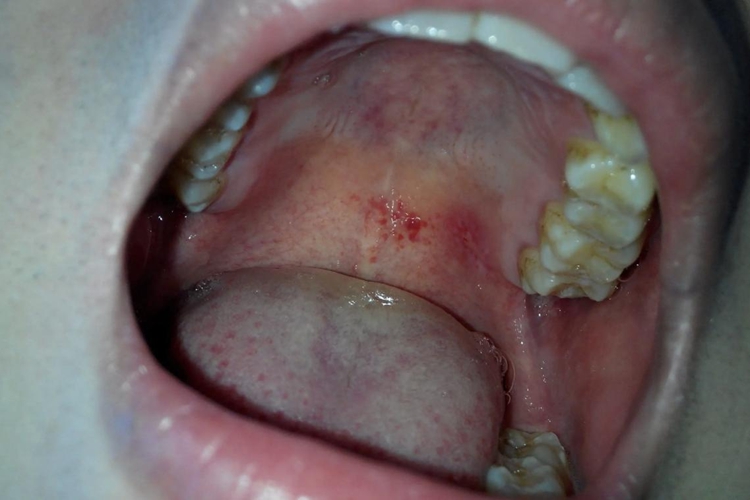

上颚即上腭,大人口腔上腭有红点,表现为病损处出现鲜红色斑点,局部充血、肿胀。

大人口腔上腭有红点,临床常见的疾病有急性咽炎、口腔红斑病、药物过敏性口炎等,不同疾病的症状表现各异。

口腔红斑病

口腔黏膜上出现鲜红色斑片,似天鹅绒样,边界清晰。发病部位以舌缘部最多见,腭部次之。皮损处表面光滑、发亮,约为0.5-2cm大小,平伏或微隆起,红斑区内有时也可看到外观正常的黏膜。